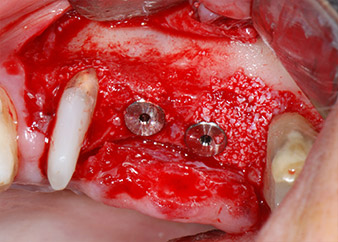

The implants (Restore, Keystone Dental, diameter 3,75 mm, length 8.0 mm) were placed with the implant motor

(Figs. 11 and 12).

Low speed insertion of implant 26

Fig. 11: Low speed insertion of implant 26 with a torque limitation of 35 Ncm.

ready for the cover screws

Fig. 12: Both implants in place and ready for the cover screws.